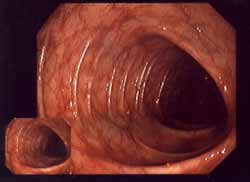

-- enfermedades inflamatorias intestinales como colitis ulcerosa (afectados son partes de la pared intestinal) y enfermedad de Crohn (afectadas son fibras reticlinas de la pared intestinal) (eso fue descrito la primera vez en los años 1920s)